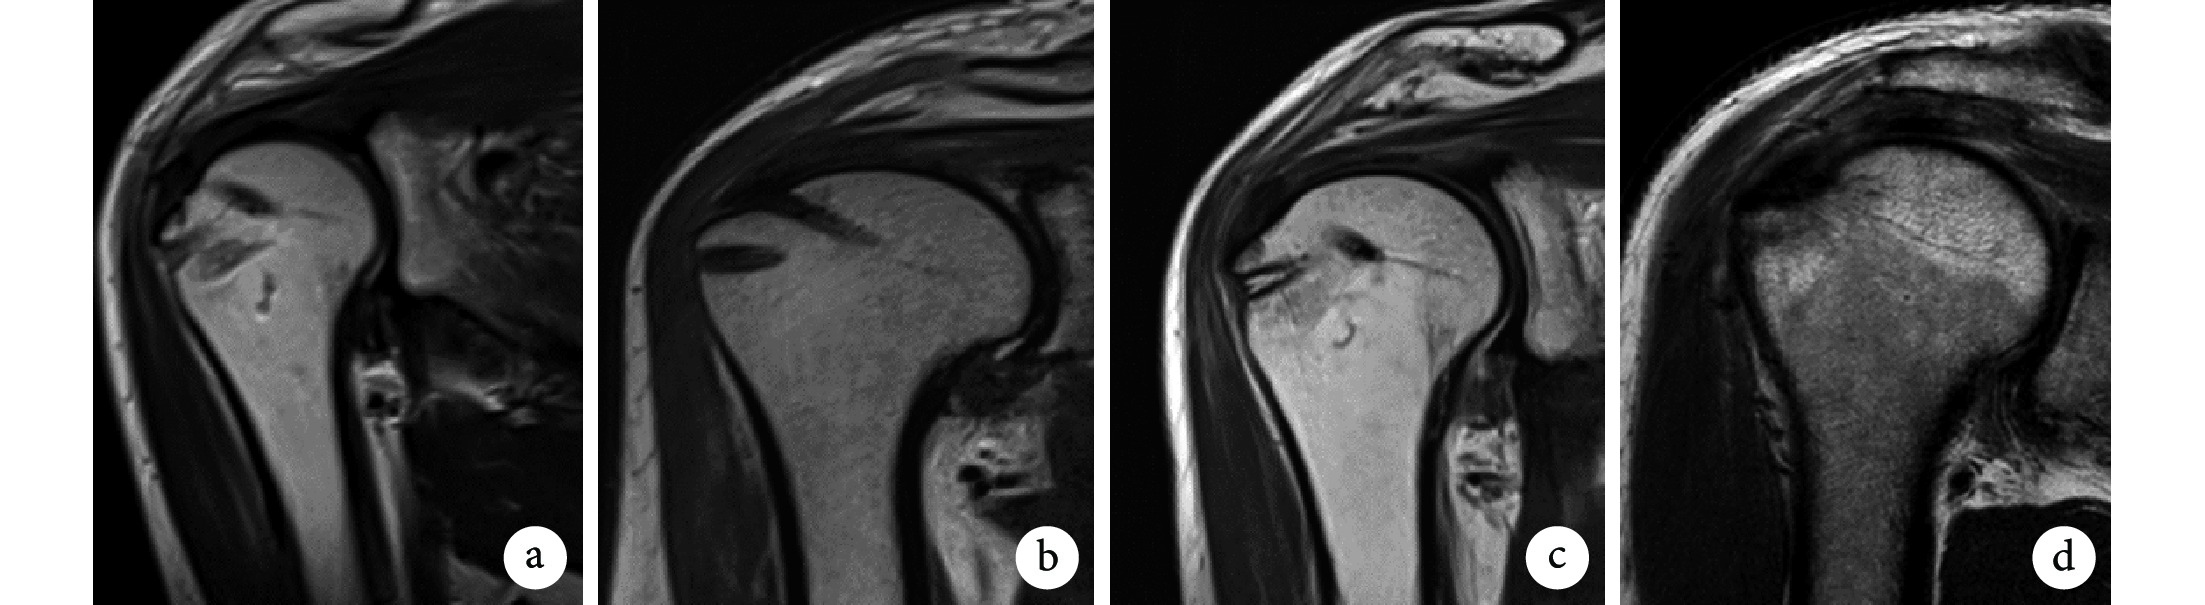

比較兩組患者術前,術后6周及3、6、12個月的VAS評分、Constant-Murley評分(包括主觀影響、疼痛、前屈、內旋、外旋、外展、肌力評分);各時間點行功能MRI檢查,將超短回波時間(ultrashort-echo-time,UTE)-T2* 技術用于計算T2* 值行定量評估,直觀反映組織的含水量及膠原纖維的空間排列,從而體現肩袖組織愈合情況(圖3)。術后12個月使用常規MRI序列進行復查,通過Sugaya分型標準[11]評價肩袖愈合情況。其中,Ⅰ型:岡上肌肌腱厚度正常,肌腱走行區呈均勻低信號;Ⅱ型:岡上肌肌腱厚度正常,但肌腱走行區出現部分高信號影;Ⅲ型:岡上肌肌腱厚度變薄,但走行區信號無中斷;Ⅳ型:岡上肌肌腱走行區信號出現部分不連續;Ⅴ型:岡上肌肌腱走行區信號完全中斷,岡上肌肌腱再撕裂。見圖4。

a. Ⅰ型;b. Ⅱ型;c、d. Ⅲ型

Figure4. Schematic diagram of some Sugaya classificationa. Type Ⅰ; b. TypeⅡ; c, d. Type Ⅲ